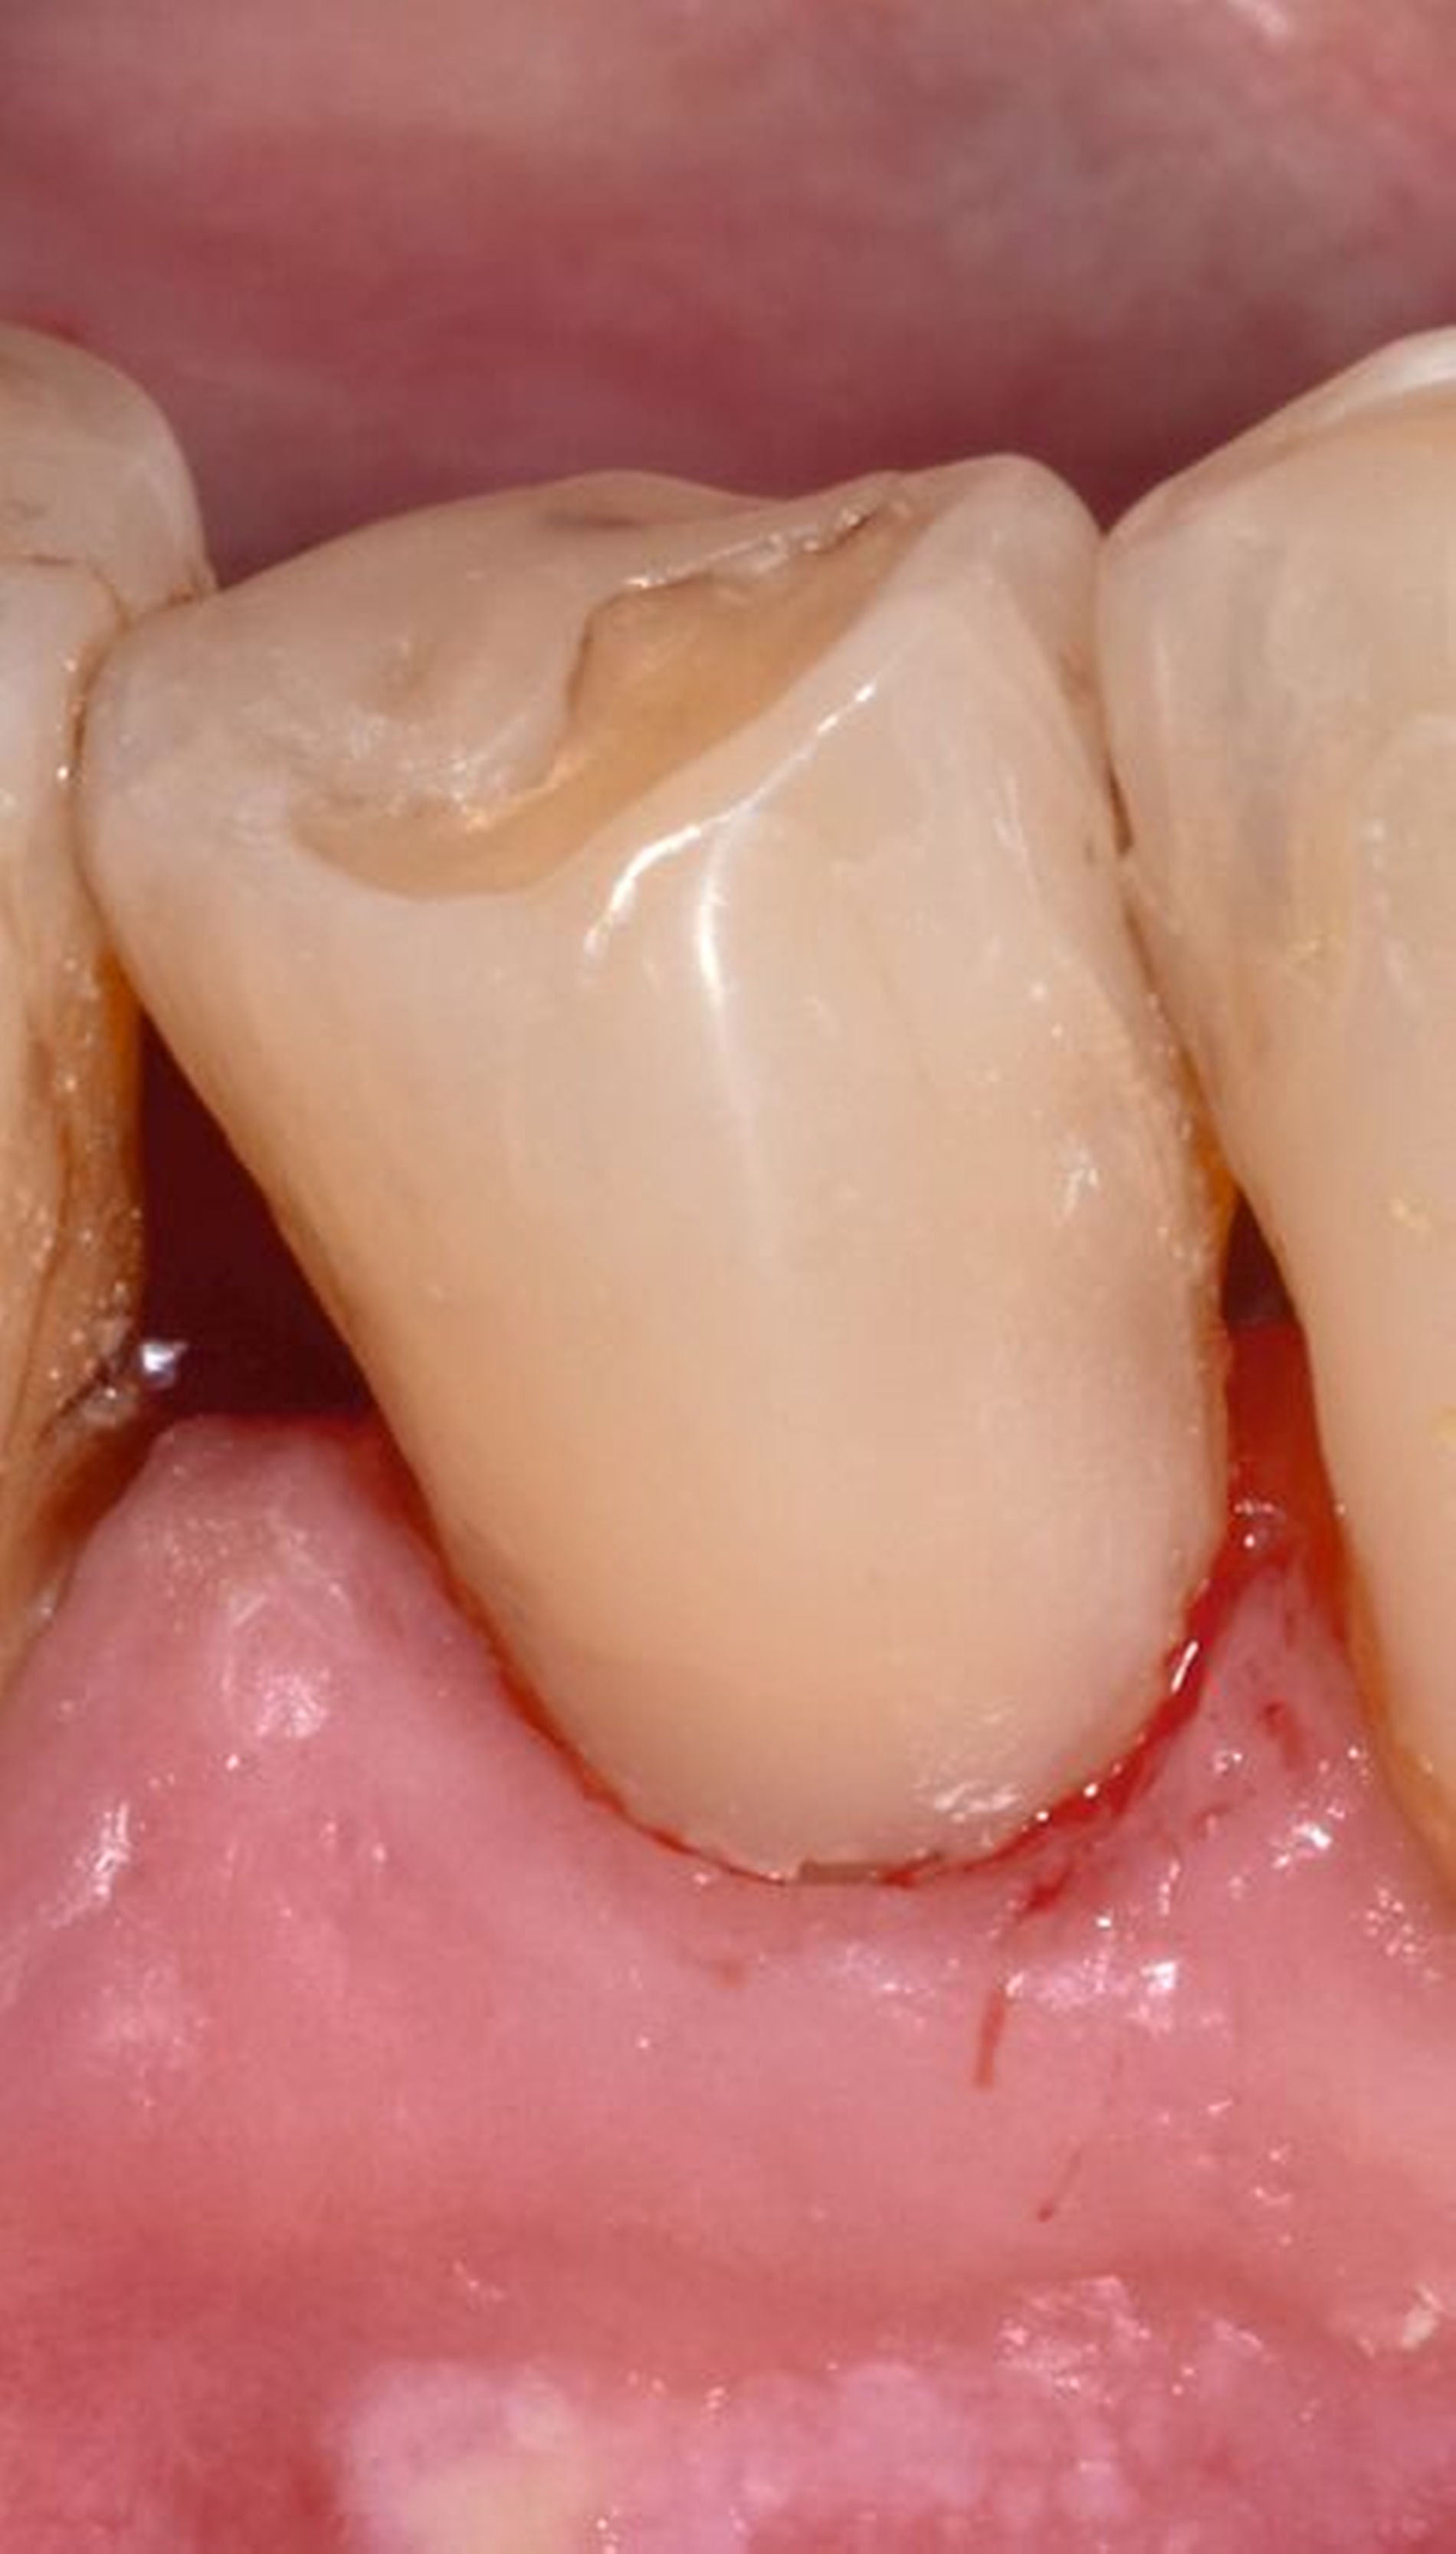

Die anschließende Ausarbeitung und Politur von Kompositrestaurationen ist erforderlich, um die Form der Restauration anatomisch korrekt zu gestalten, Überhänge, die einen Reiz für die umgebenden Weichgewebe darstellen können, zu entfernen und die Oberfläche zu glätten und somit zu vergüten. Polierte Kompositoberflächen sind widerstandsfähiger gegen Alterungs- und Abnutzungsvorgänge in der Mundhöhle. Raue Kompositoberflächen fördern die Plaqueakkumulation (Abbildung 3) und somit die Verfärbungstendenz des Materials. Die Glanzretention ist jedoch limitiert und je nach Ausgangsmaterial und Polierprozess unterschiedlich lang anhaltend.